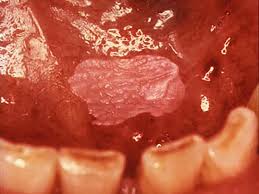

/ How To Get Rid Of Leukoplakia On Tongue - Oral leukoplakia is the most common chronic keratotic lesion of the oral cavity and is potentially premalignant.1,2 it is a clinical diagnosis and is characterized predominantly by adherent white plaques of the oral mucosa.3.

In the oral cavity there is a feeling of tightness and dryness, burning, irritation. Leukoplakia appears as thick, white patches on your gums or on the within your cheeks. Some of the known causes being smoking, tobacco, alcohol, bacterial/fungal infection, uv radiation etc. Read through for more information of how the bumps look like and available treatment oral leukoplakia appears as white patches on the mucus membrane lining the inside mouth, the tongue, mouth roof and inside cheeks. It is the mouth's reaction to chronic irritation of the mucous membranes of.

Pin On Anatomy 001 from i.pinimg.com Read through for more information of how the bumps look like and available treatment oral leukoplakia appears as white patches on the mucus membrane lining the inside mouth, the tongue, mouth roof and inside cheeks. Treatment, if needed, involves removing the source of irritation. Leukoplakia are patches on the tongue, in the mouth, or on the inside of the cheek. Removing the source of irritation may cause the patch to disappear. There are a few conditions that are linked to a white tongue you can have even. How to get rid of diseases of the oral cavity. Oral diseases are very common in all age groups and genders and arise from infections in the mucosal lining in most cases. How then do you get ease the pain and get rid of the bumps on your tongue?